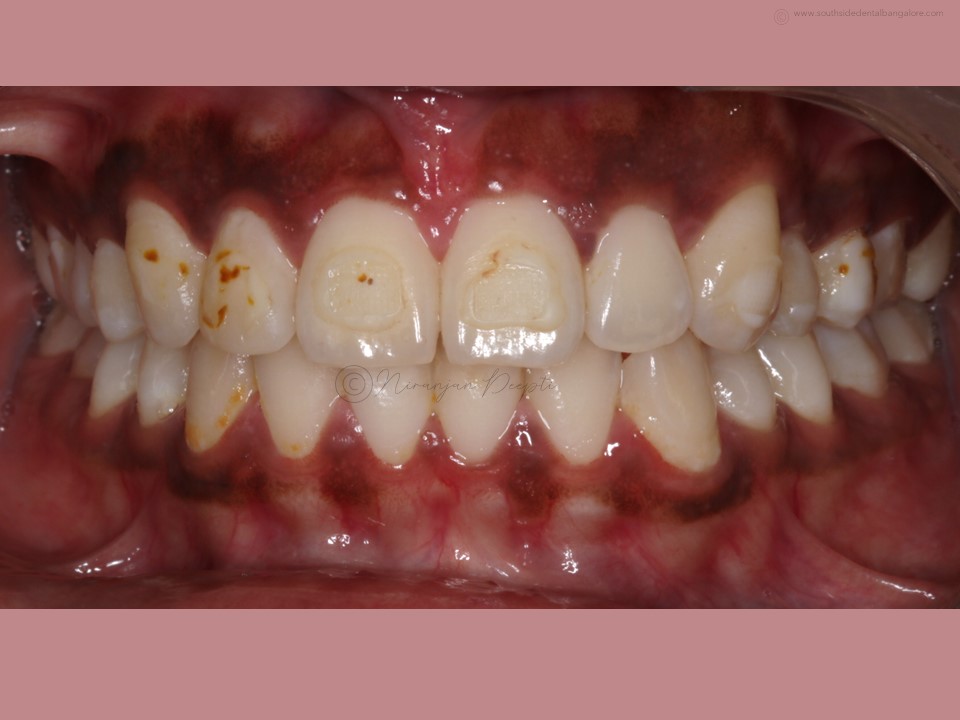

Polishing of teeth after the debonding of braces is a crucial step in the orthodontic treatment process.

- Smoother Surface: Braces leave adhesive residue and small imperfections on the tooth surface. Polishing helps smoothen these areas, reducing the risk of plaque accumulation and making it easier to clean teeth effectively.

- Minimizes Staining: Residual bonding materials and rough surfaces can attract stains, affecting the appearance of your smile. Polishing removes these stains and restores the natural luster of your teeth.

- Enhances Aesthetics: Polishing creates a polished, uniform appearance, enhancing the overall aesthetics of your smile and boosting your confidence post-braces.

- Scaling: Before polishing, your orthodontist may perform scaling to remove any hardened plaque or calculus deposits that have accumulated during the braces treatment.

- Polishing: Using a specialized dental tool, your orthodontist/dentist will carefully polish each tooth surface to remove any remaining adhesive residue and smooth out imperfections.